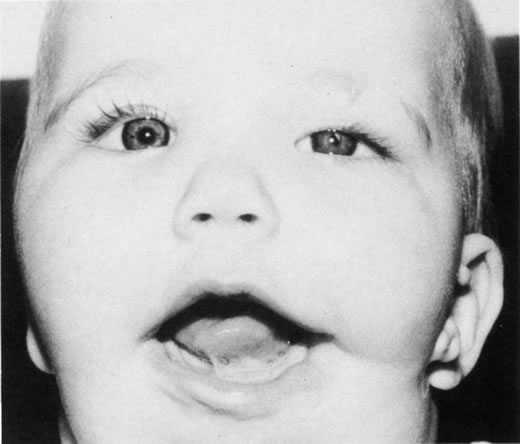

Anophthalmos and microphthalmos are usually unilateral and may be associated with a variety of craniofacial and systemic anomalies, including orbital hypoplasia, facial clefts, basal encephalocele, hemifacial microsomia, mandibulofacial dysostosis, cardiac anomalies, polydactyly, and mental retardation. When they occur unilaterally, they also can be associated with anomalies of the contralateral “normal” eye, including cataract, cornea1 opacities, microphthalmos, coloboma, epibulbar dermoids, and nystagmus. Anophthalmos and severe microphthalmos frequently are associated with contracted conjunctival fornices, phimotic eyelids, and generalized hypoplasia of the periocular soft tissues (Fig. 1). When soft tissue contractures occur, the early use of conformers is essential to expand these tissues.2 This treatment should be instituted in the first month of life, with progressive enlargement of the conformer over time to achieve maximum expansion of the conjunctival fornix. Unfortunately, this treatment usually does not stimulate adequate orbital bone growth, and unilateral microphthalmos and anophthalmos may be associated with secondary orbital hypoplasia (Fig. 2). Serial implantation of progressively larger orbital implants or placement of expansile orbital implants has been advocated to stimulate bony orbital development.3,4